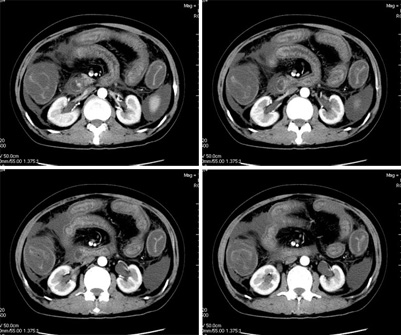

增强

真是少见!至少本人从未见过!整个消化道除了胃壁以外整套小肠及结肠肠壁均不同程度增厚水肿,肠壁间未见积气,亦未见明显的血运障碍(肠细膜上动静脉均显示很好)。盆腹腔积液。

真是少见!至少本人从未见过!整个消化道除了胃壁以外整套小肠及结肠肠壁均不同程度增厚水肿,增强明显分层[粘膜层及浆膜层明显强化,粘膜下层强化轻]。结合病史考虑肠道缺血改变[病因待查--血管炎,结缔组织疾病等]

楼主上传图像很漂亮。把每幅图像放大,增强扫描,发现肠系膜上静脉管腔变形,其内见半圆形等密度影,结合病史,考虑肠系膜上静脉栓塞并肠壁间水肿,腹水。(这是首次发的话题)

真是少见!至少本人从未见过!整个消化道除了胃壁以外整套小肠及结肠肠壁均不同程度环形增厚,肠壁密度均匀呈“晕圈”样改变,粘膜下层低密度,粘膜层和外层为相对高密度。增强强化不明显。结合病史考虑肠道急性缺血改变。腹水。形成原因肠系膜动脉栓塞、还是静脉血栓形成看不懂。

肝周、脾脏周围可见腹水,盆腔可见积液;肠管壁广泛的增厚,密度减低,可见液体积聚在粘膜下层里面,首先还是考虑血管引起的。感染放在后面吧。

肠管壁增厚,以升结肠、横结肠明显,肠袋变浅,cta显示肠系膜上动、静脉显影清楚,管腔未见狭窄,同时大量腹水,考虑:肠麻痹水肿?食物中毒?

本例ct表现是肠道的整体性充血、水肿,以结肠特别是横结肠、升结肠、盲肠为显著,横结肠一眼粗略看过去,极似极度水肿之胰腺。回肠末段亦呈明显近似结肠改变,小肠则以充血为主,水肿相对轻微。诸段肠管无明显如溃疡、出血等局部损害,重度腹水。肝脏体积变小,肝裂增宽,以肝圆韧带为明显。肝脏各部比例尚正常,无局部外突或内凹,密度均匀一致。胆囊增大,所给图片及楼主已经仔细观察过,肝段下腔静脉肠系膜静脉均正常。